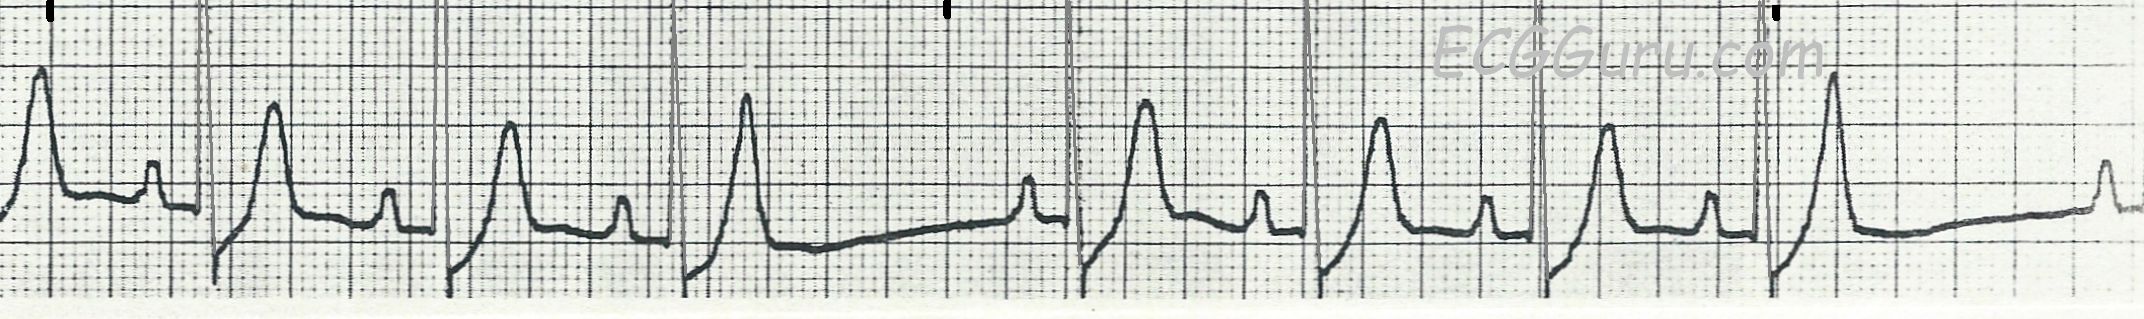

The ECG:  There are a rhythm strip with two leads, II and III, and also a standard 12-lead ECG. The RHYTHM STRIP shows a tachycardiac rhythm that slows very slightly toward the end.  The rate is around 107 bpm, with an R to R interval of approximately 543 ms in the earlier, regular portion.  There are regular P waves present, all followed by QRS complexes.  Most of the QRS complexes are normal width, but the 2nd, 5th, and 8th are slightly wide at 130 ms, or .13 seconds.

These wider QRS complexes represent aberrant conduction with LBBB occurring intermittently.  Aberrant conduction often occurs due to a faster heart rate, but the only clue here is the intermittent conduction disturbance seems to disappear when the rate slows very slightly.  It is hard to determine mechanism of aberrant conduction when we have only a ten-second rhythm strip.

The 12-LEAD ECG  has essentially the same rate and rhythm, except all the beats in the first ¾ of the ECG are conducted aberrantly, in a LEFT BUNDLE BRANCH BLOCK pattern.  This indicates that the LBB is refractory at this time.  Beat No. 15 is premature (PAC).  The pause after the PAC allows the left bundle branch to repolarize, conducting one single beat normally.